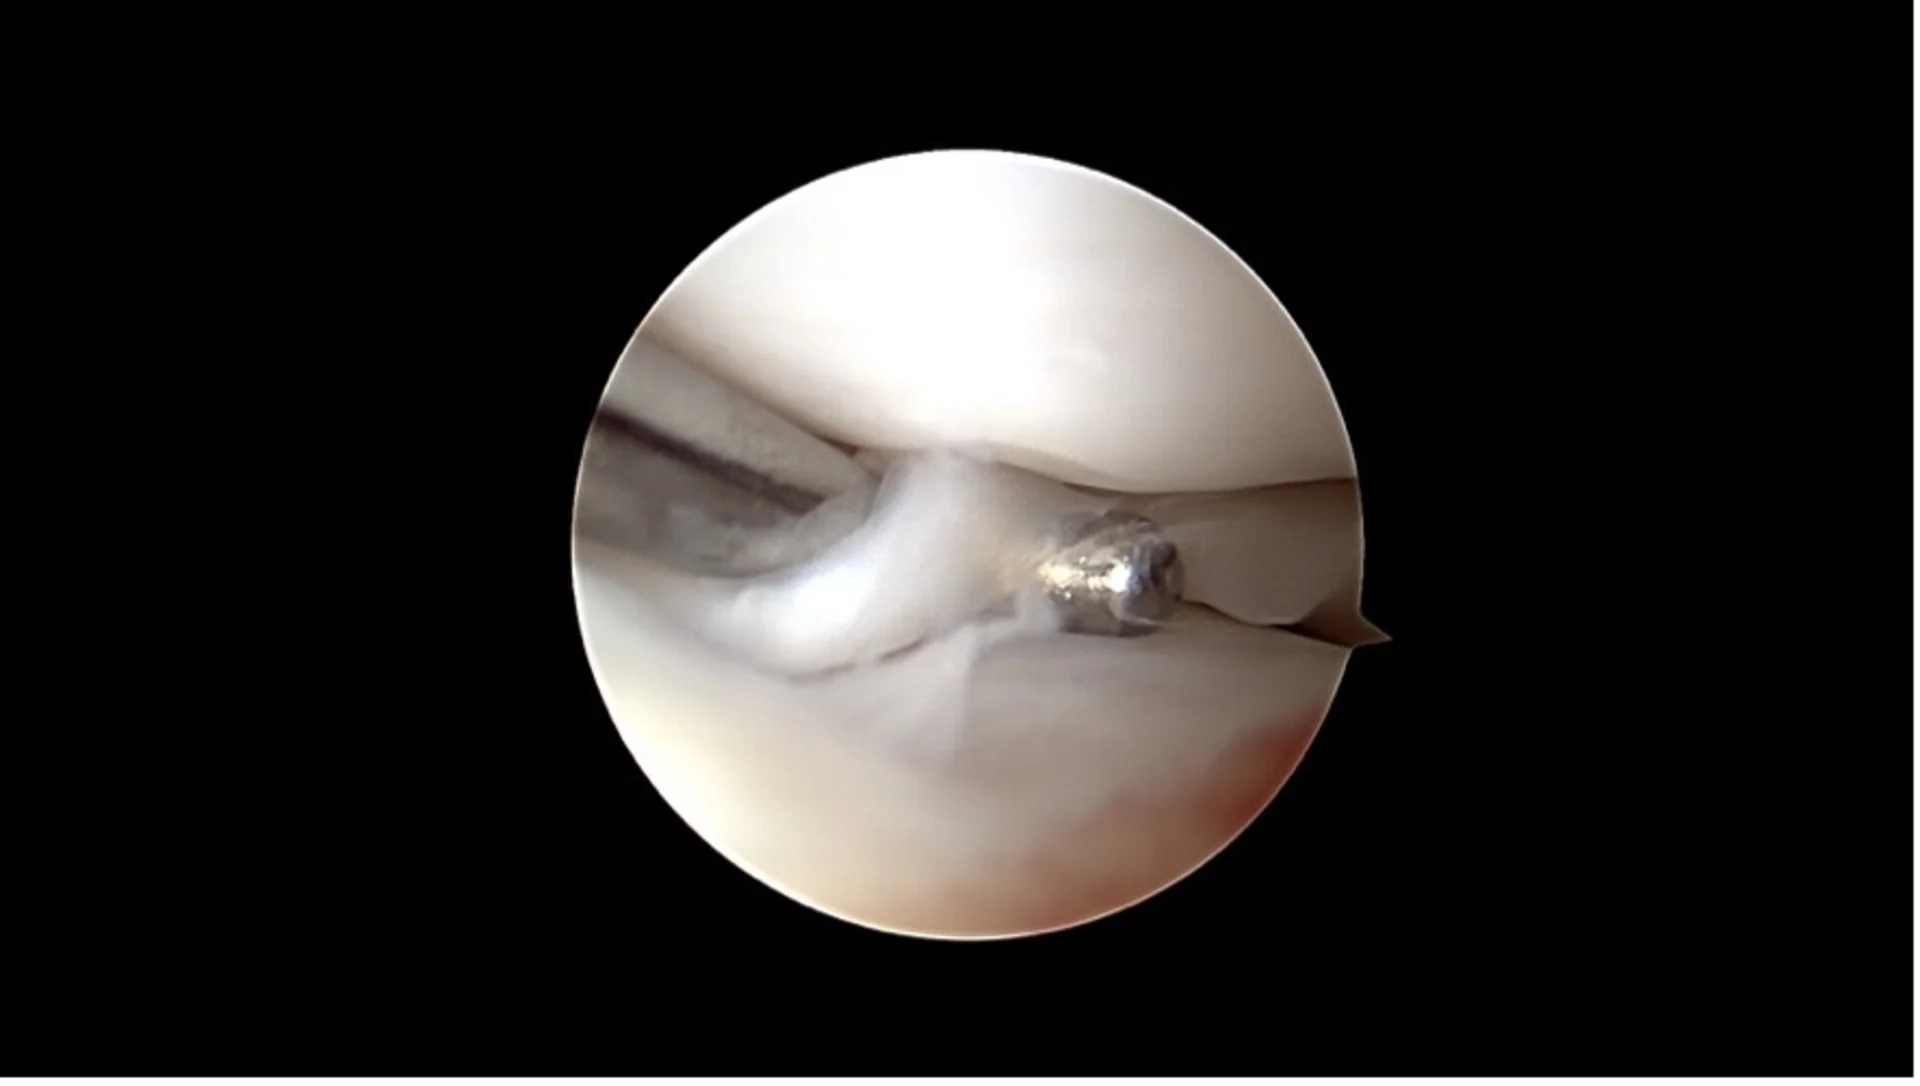

A miniature camera allows direct visualization of the inside of the joint through small skin incisions. Changes to the cruciate ligament and associated damage such as meniscal tears can be diagnosed and in many cases treated immediately.

Basket-handle meniscus tear